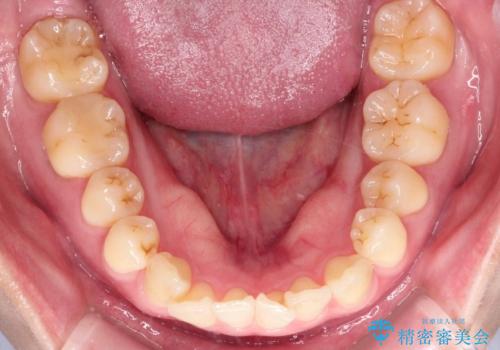

- 「下の前歯が斜めになっている」を主訴に来院された患者様です。

下顎前歯に叢生があり、右上2は反対咬合の状態でした。

抜歯は行わずインビザラインで治療を行いました。